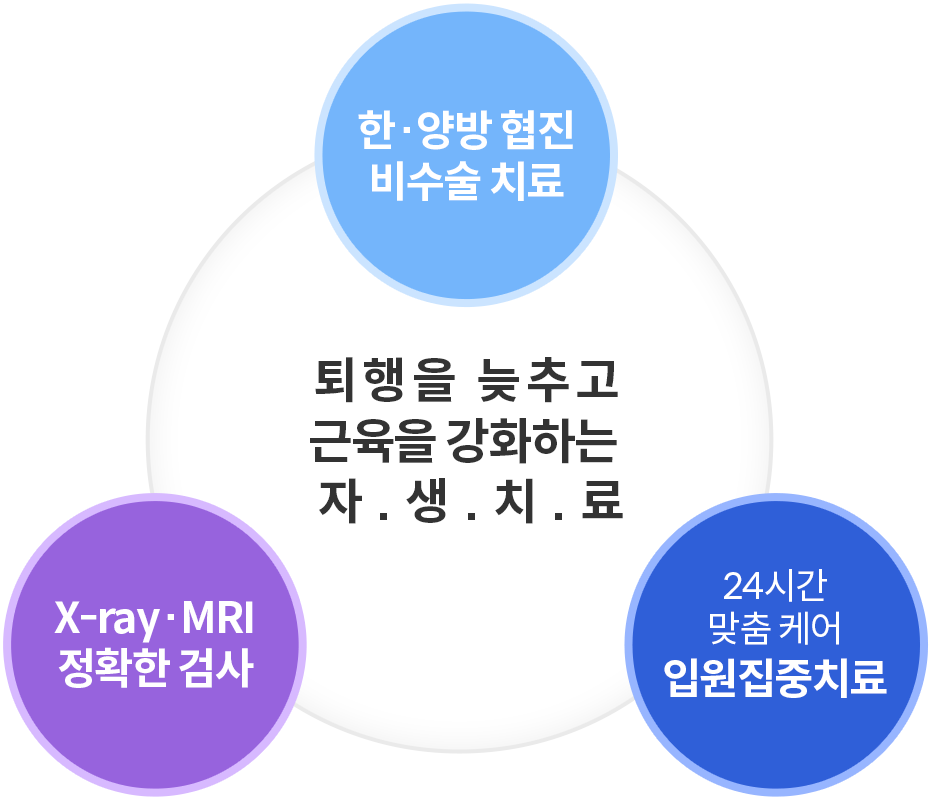

과학적으로 입증된 한약 치료 효과, 더 이상의 퇴행을 막아 노후 삶의 질을 높여드립니다.

내 척추·관절로 오래 건강하게!

통증 제거는 물론 퇴행 속도를 지연시켜 척추·관절을 최대한 오래 건강하게 유지하는 것을 목표로 치료합니다.

자생 퇴행성 척추·관절 질환 주요 치료법